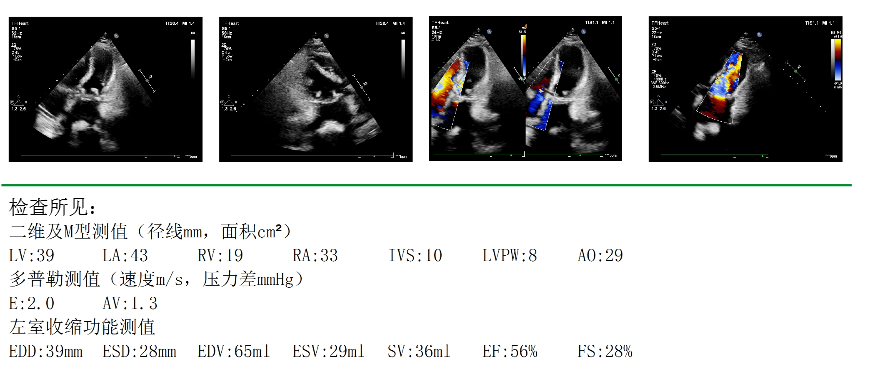

△术前心脏彩超

67岁的江阿姨(化名),最近1年来持续出现活动后心累、心慌等症状,于10月中旬来到华西天府医院心脏大血管外科方智副主任医师处就诊。心脏彩超提示,江阿姨先天性镜面右位心风湿性心脏病,二尖瓣中-重度狭窄,三尖瓣轻-中度反流。